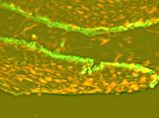

La IFD realizada en la Cátedra de Dermatología del Hospital de Clínicas demostró: depósitos lineales en membrana basal de Ig G (Fotos 11 y 12), Ig A (foto 13) y C3.

Foto 11 IFD: presencia lineal IgG

Foto 12 IFD: presencia lineal IgA

Foto 13 IFD: presencia lineal C3

Diagnóstico definitivo: penfigoide de membranas mucosas en una paciente portadora de artritis reumatoidea.